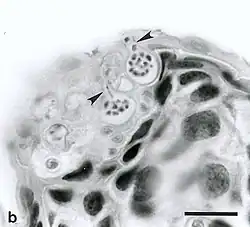

L’infection est transmise dans l’eau, par des zoospores qui colonisent la peau des amphibiens où ils forment des zoosporanges, lesquels produiront de nouveaux zoospores qui infecteront d'autres amphibiens ou d'autres parties du corps de l'animal infecté.